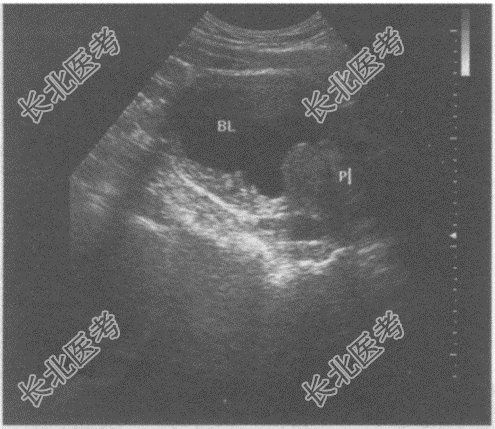

- 单项选择题临床资料:男, 60岁,自述排尿分叉、不畅, 患慢性前列腺增生十余年。

超声综合描述:横切4: 00~8:00处可见扁平形中等回声区, 表面粗糙,内回声不均, 最大厚度1.1cm,后方无声影, 体位变动形态无改变。

超声提示: A、膀胱实性占位

B、膀胱沉积物

C、腺性膀胱炎(轻度弥漫增厚型)

D、膀胱结石

E、膀胱肿瘤